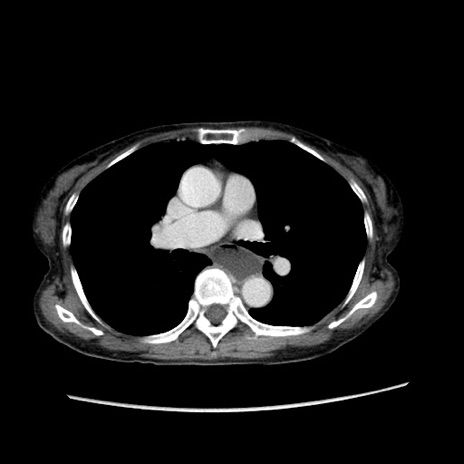

冠状断像